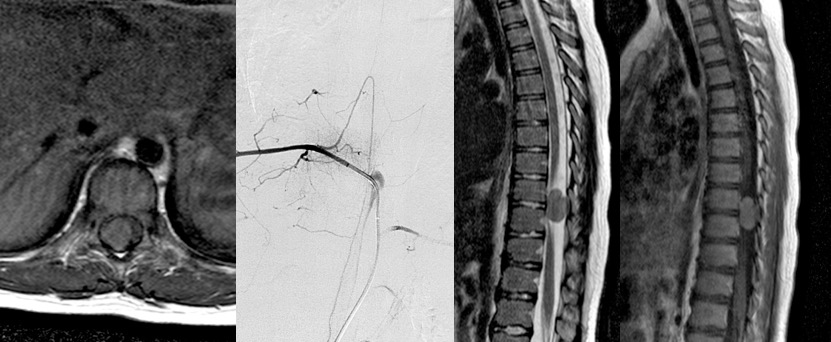

- l’artériographie est nécessaire lorsque la lésion intéresse l’étage thoracique moyen, (en particulier T9 gauche) pour ne pas risquer de léser l’artère d’Adamkiewicz, quand la chirurgie risque de nécessiter un sacrifice radiculaire ou qu’il existe une extension foraminale.

méningiome dans la NF2, angiographie montrant l’artère d’Adamkiewicz et le blush tumoral